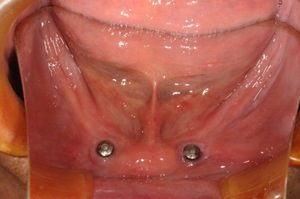

「2本のインプラントと高精度な総義歯で噛める入れ歯を!」 数十年前でしたら歯をすべて失った方は総義歯しかなかったのですが、近年は医療技術の進歩により治療方法の選択肢が増えました。 方法によっては審美性・噛む力・装着感もか […]

上下総入れ歯使用中の患者さんです。旧義歯が破折したために来院されました。 下の総義歯が浮き上がり安定しない状態でした。 一般的に上の総義歯は比較的容易に安定が得られますが、下の総義歯は通常安定が得られないことが多いです。 […]